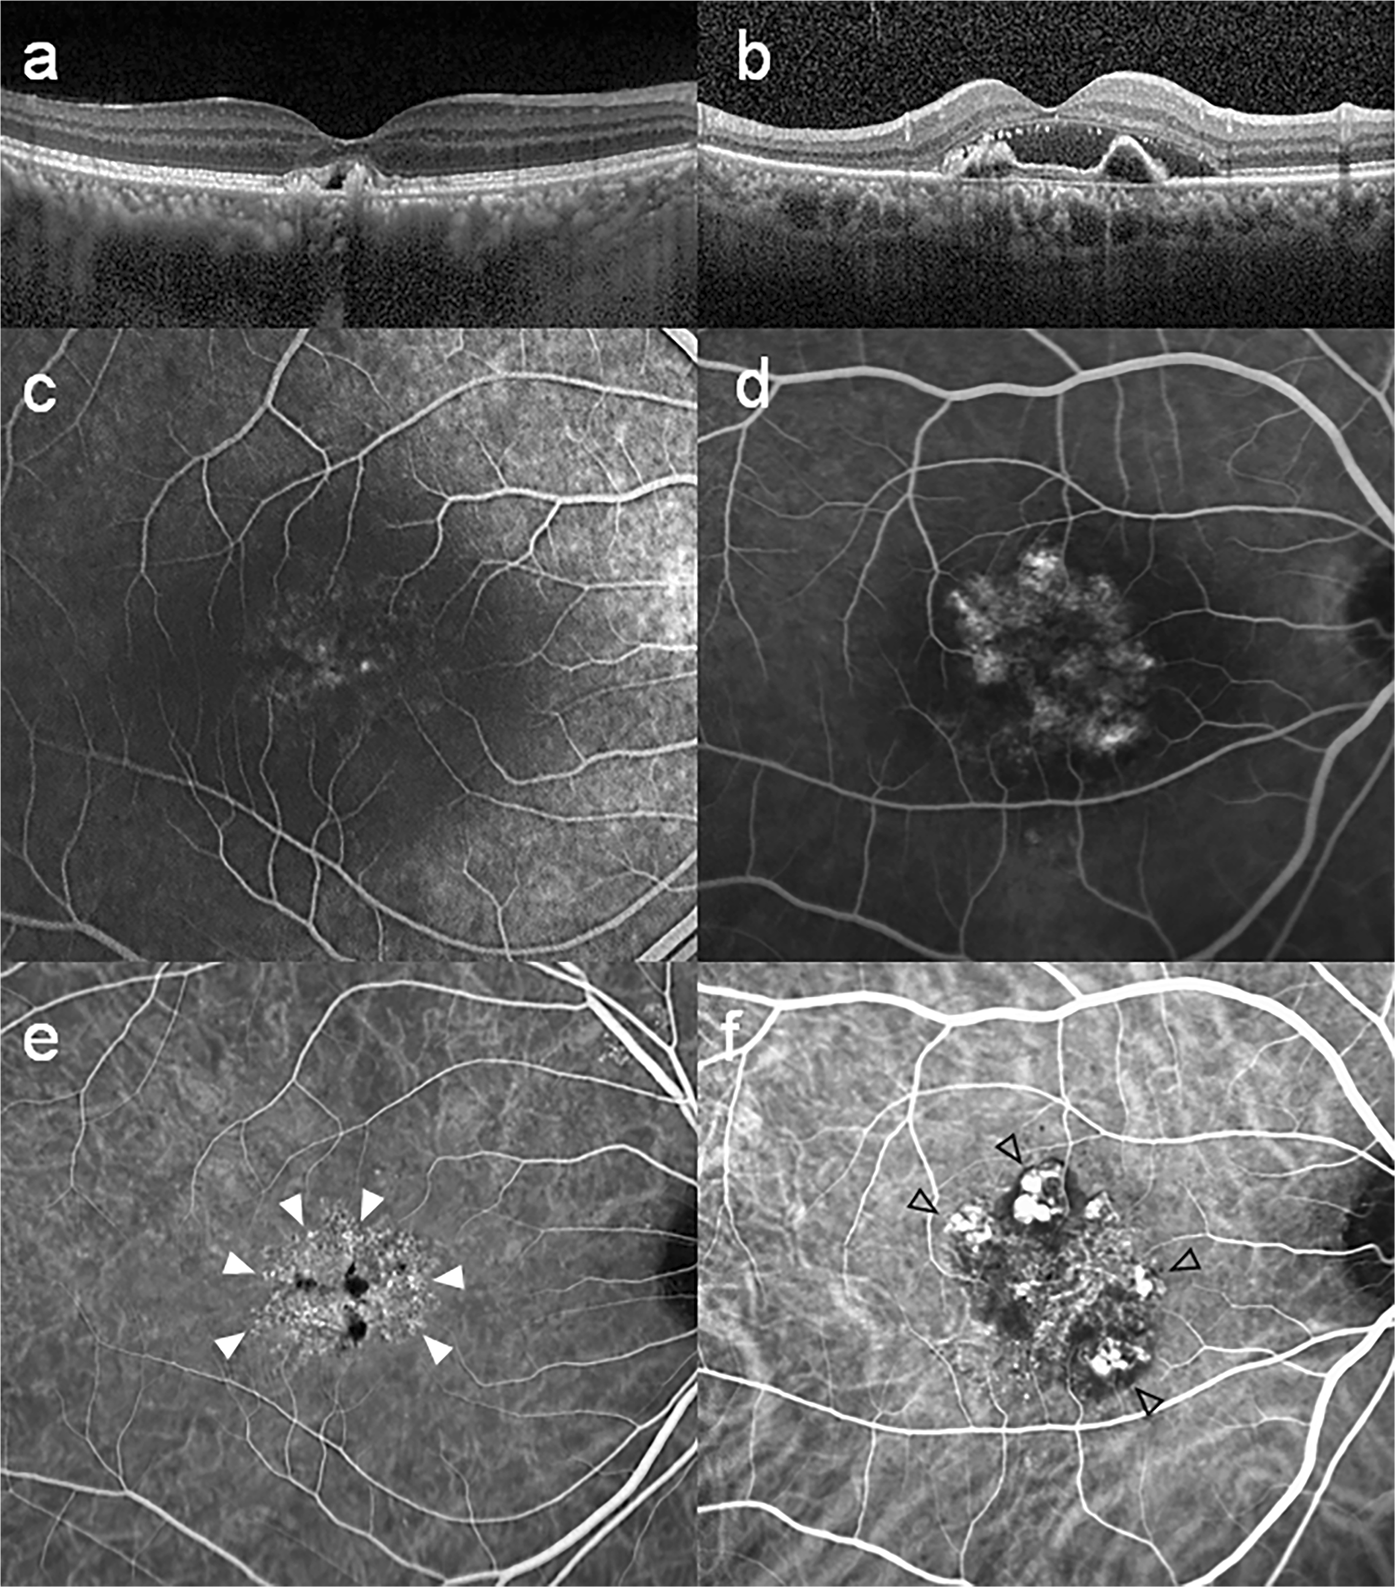

Figure 3

Multimodal imaging of a 53-year-old male with microaneurysmal choroidal vasculopathy (MCV, left column) and 66-year-old male with polypoidal choroidal vasculopathy (PCV, right column). (a) Spectral domain optical coherence tomography (OCT) showing pigment epithelial elevation overlying a markedly thickened choroid and dilated choroidal vessels with minimal subretinal fluid. (b) Moderately thickened choroid is shown on OCT, and there is a discrete polypoidal structure between retinal pigment epithelium and Bruch’s membrane. (c,d) Early fluorescein angiography showing leakage from the choroidal neovascularization corresponding to the hyperfluorescent spots in indocyanine green angiography (ICGA). (e) ICGA in the early phase showing branching vascular network. Note that there is no definite polyp, other than small aneurysmal dilations (white arrow heads). (f) ICGA demonstrates multiple hyperfluorescent spots around the fovea corresponding to the polyps (opened black arrow heads) of PCV.